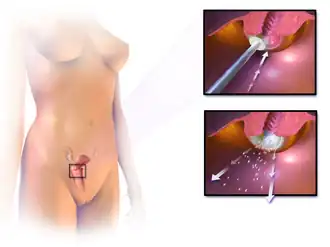

Treatment

Treatment for CIN 1, mild dysplasia, is not recommended if it lasts fewer than two years.[20] Usually, when a biopsy detects CIN 1, the woman has an HPV infection, which may clear on its own within 12 months. Therefore, it is instead followed for later testing rather than being treated.[20] In young women, closely monitoring CIN 2 lesions also appears reasonable.[6]

The typical threshold for treatment is CIN 2+, although a more restrained approach may be taken for young persons and pregnant women. Treatment for higher-grade CIN involves removal or destruction of the abnormal cervical cells by cryocautery, electrocautery, laser cautery, loop electrical excision procedure (LEEP), or cervical conization.[21] While these surgical methods effectively reduce the risk of developing cervical cancer,[22][23] they cause an increased risk of premature birth in future pregnancies.[24][25] Surgical techniques that remove more cervical tissue come with less risk of the cancer recurring but a higher chance of giving birth prematurely. Due to this risk, taking into account the age, childbearing plans of the woman, the size and location of the cancer cells are crucial for choosing the right procedure.[22][23]

While retinoids are not effective in preventing the progression of CIN, they may be effective in causing regression of the disease in people with CIN2.[26] Therapeutic vaccines are currently undergoing clinical trials. The lifetime recurrence rate of CIN is about 20%, but it isn't clear what proportion of these cases are new infections rather than recurrences of the original infection.

Research to investigate if prophylactic antibiotics can help prevent infection in women undergoing excision of the cervical transformation zone found a lack of quality evidence.[27]